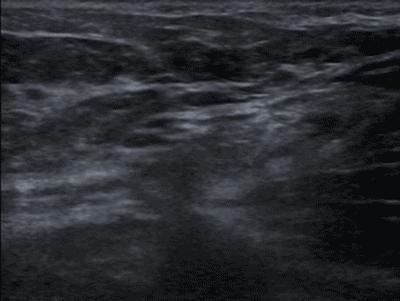

Echografie; hernia inguinalis

Figuur 4. Hernia inguinalis (verricht tijdens Valsava gevolgd door compressie).

Echografie werkt door middel van geluidsgolven, welke niet schadelijk zijn (zie college Echo Techniek). Het is snel, non-invasief en vrijwel altijd beschikbaar. Het is met name geschikt voor de beoordeling van weke delen en wordt het meest toegepast in het abdomen, de mammae, het scrotum, de hals of het skelet/bewegingsapparaat. Het is een dynamisch onderzoek waarbij er bijvoorbeeld gekeken kan worden naar de peristaltiek van de darmen, beweegbaarheid van een structuur (bv een steen in de galblaas of hernia inguinalis) en de comprimeerbaarheid van een structuur (bv appendix, galblaas of venen in armen en benen), zie figuur 4.